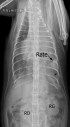

RadioQuiz 22 – Réponse

EchoQuiz 9 – Voilà pourquoi mon labrador n’urine pas bien

RadioQuiz 21- Réponse

RadioQuiz 20 – Réponse

RadioQuiz 19 – Réponse

RadioQuiz 18- Réponse

ÉchoQuiz 8 – Réponse

EchoQuiz 7 – Réponse ouverte à tous

RadioQuiz 17 – Réponse